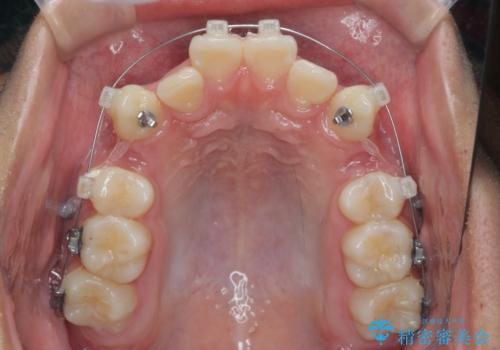

- 前歯のがたつきが原因で歯ブラシしづらい、見た目を改善したい!と矯正治療を希望され来院されました。

スペースの不足が見られるため、小臼歯の4本抜歯を行いマルチブラケットを用いた矯正治療を計画します。

噛み締めが強く、治療に時間がかかりましたが矯正治療の仕上がりに満足いただくことができました。